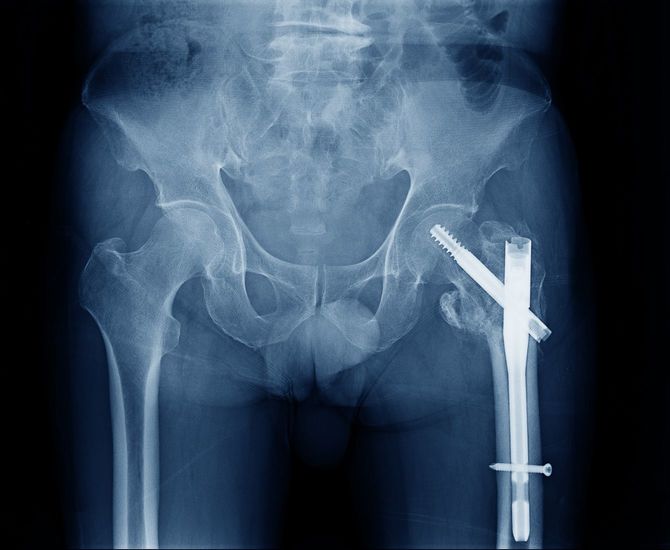

8年後、89歳になった母親は、部屋で転んで大腿骨を骨折し、4カ月の入院。これをきっかけに要介護4に介護度が上がり、家の中でも手引きで歩く状態に。